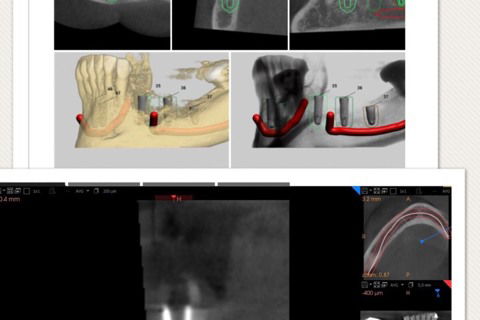

Planejamento virtual e tomografia final

tomografia final comprovando quês técnica é segura e precisa